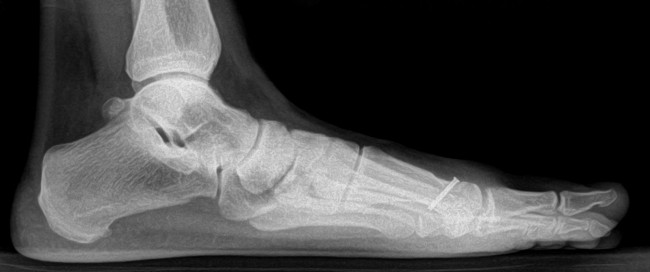

The goal of this study was to identify the prevalence of vitamin D deficiency in patients with a low energy fracture of the foot or ankle.

Methods: Over a 6-month period, a serum 25-OH vitamin D level was obtained from consecutive patients with a low energy ankle fracture, fifth metatarsal base fracture, or stress fracture of the foot or ankle. For comparative purposes, vitamin D levels in patients with an ankle sprain and no fracture were also examined.

Results: The study cohort included 75 patients, of which 21 had an ankle fracture, 23 had a fifth metatarsal base fracture, and 31 had a stress fracture.